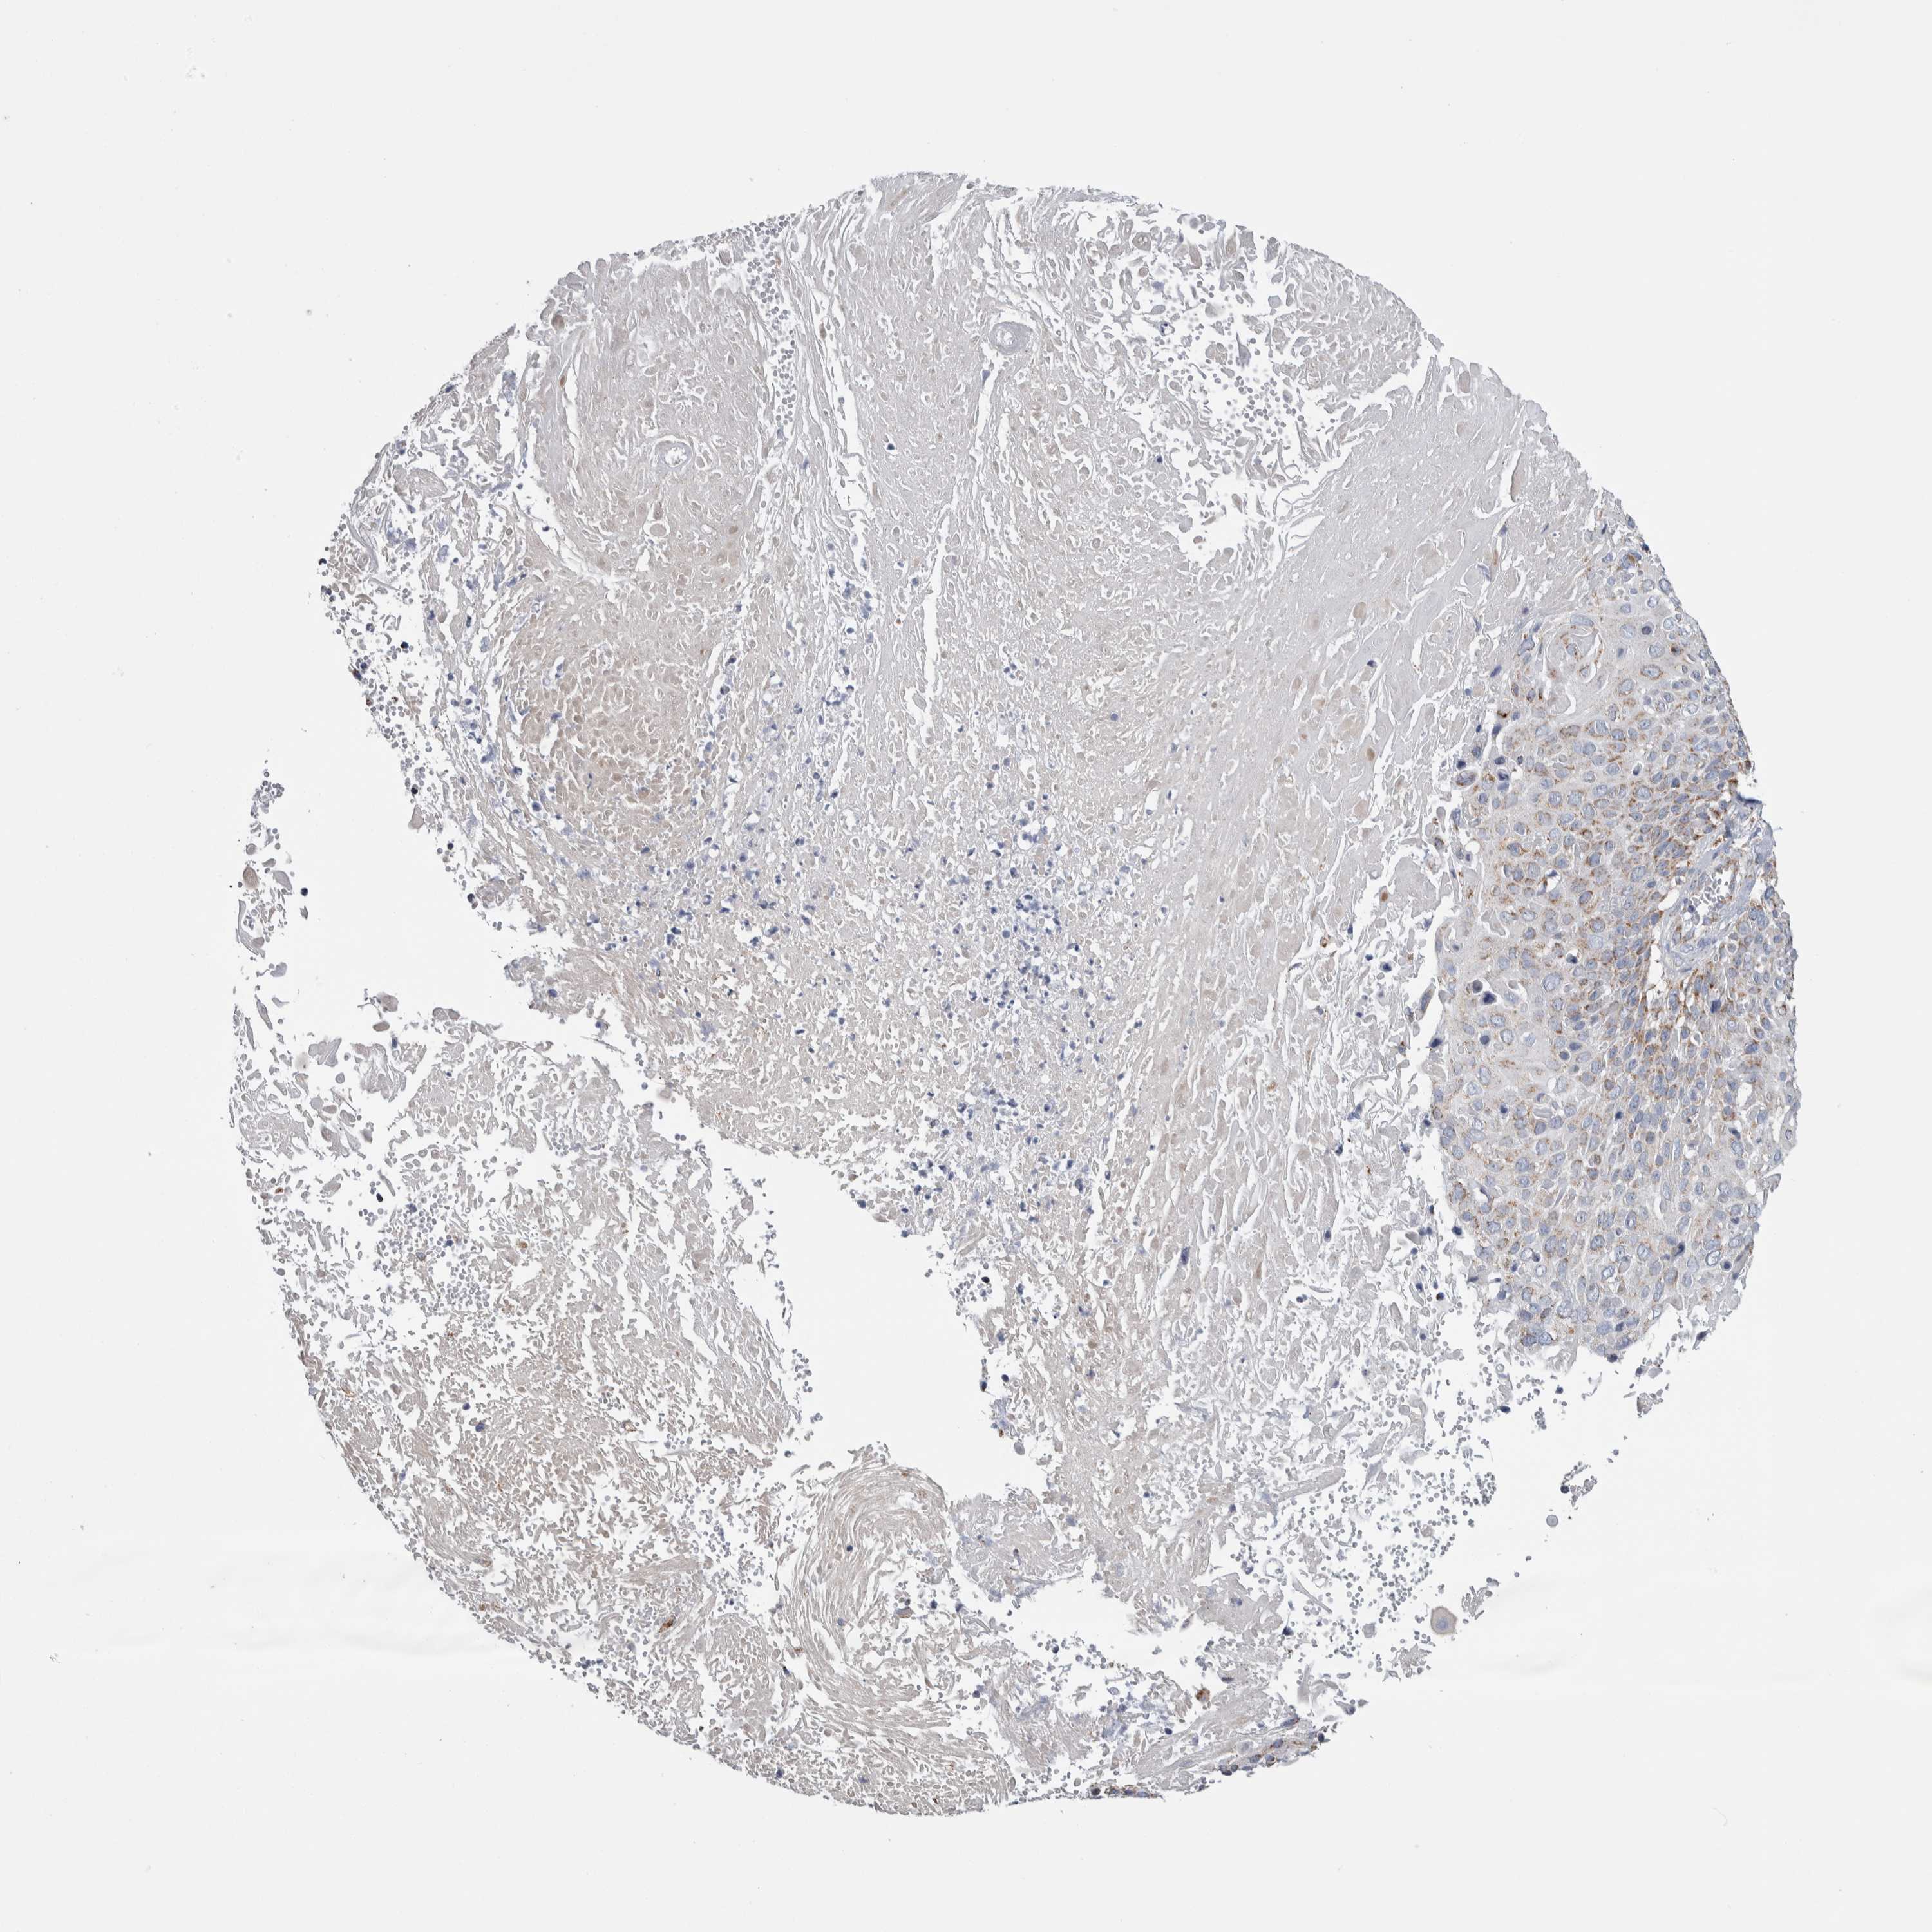

CERVICAL CANCER - Protein expressioni

A mouse-over function shows sample information and annotation data. Click on an image to view it in a full screen mode. Samples can be filtered based on level of antibody staining by selecting one or several of the following categories: high, medium, low and not detected. The assay and annotation is described here.

Note that samples used for immunohistochemistry by the Human Protein Atlas do not correspond to samples in the TCGA dataset.

Antibody stainingi

Antibody staining in the annotated cell types in the current human tissue is reported as not detected, low, medium, or high, based on conventional immunohistochemistry profiling in selected tissues. This score is based on the combination of the staining intensity and fraction of stained cells.

Each image is clickable and will lead to virtual microscopy that enables deeper exploration of all samples and also displays staining intensity scores, fraction scores and subcellular localization as well as patient and tissue information for each sample.

Antibody HPA018990

Antibody HPA018993

Antibody HPA018996

Antibody HPA024089

Squamous cell carcinoma, NOS

Adenocarcinoma, NOS